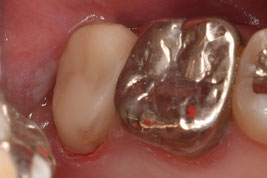

デンタル上で17根尖部から遠心にかけて透過像を認めました。歯冠遠心部はう蝕で崩壊しており、一見すると保存不可能に見える状態です。補綴物を撤去し、軟化象牙質を慎重に除去したところ、近心には十分な健全歯質が残存し、遠心にも健全歯質を保存することができました。レントゲンはあくまで画像であり、実際の状態と相違がある場合があります。レントゲンだけで判断する危険性を、改めて実感しました。

隔壁を作成しラバーダム防湿にて根管治療を施術しました。根管内からは多量の排膿を認めました。初回では可能な限り根管内から排膿させ、水酸化カルシウム製剤を貼薬して仮封しました。仮封すると圧力が高まり、疼痛の原因となりますが、再感染を防ぐために排膿を認めた場合であっても仮封します。ただし、強い疼痛が発現した場合は開放します。